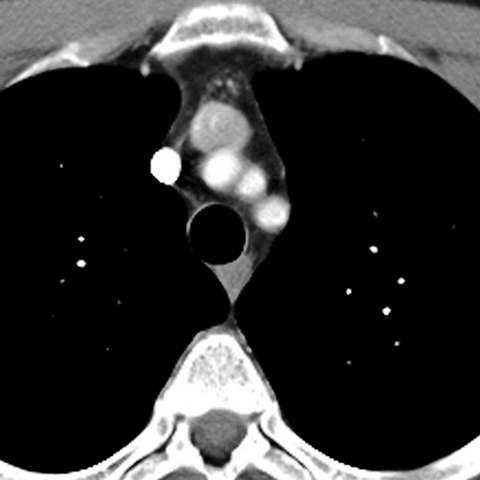

Normal Mediastinum (Axial CT) [2 of 5]